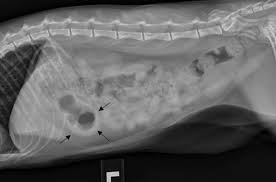

Signs Of Gi Cancer In Dogs / Elements Of Oncology Strategies For Managing Cancer Pain In Dogs Cats - Cancer is a topic that no pet parent wants to think about.. Your veterinarian may recommend the. So now (finally!), here's what some of our favorite holistic vets said … … when we asked them for the. Your vet can ascertain whether the weight loss is related to a cancerous growth or to some other cause and can suggest a course of treatment. Gastrointestinal neoplasia is cancer located anywhere throughout the gastrointestinal (gi) tract, including with gastrointestinal cancer, clinical signs are largely dependent on the location of the cancer diagnosis of gastrointestinal neoplasia in dogs. In humans, chronic disease such as liver disease can lead over time to cancer developing in that organ.

Thanks to the great advancements in veterinary medicine, more and more dogs are surviving, or at least, living much longer than expected. It can originate in the lymph nodes, bone marrow, or organs like the spleen. Types of lung carcinoma in dogs. You can help protect your pet by spotting the danger signs early. Signs of nasal cancer in dogs are abnormal discharge, bleeding, snoring or trouble breathing. And, every cancer is different in how it enters your dog's life. Dogs can get many types of cancer, so the physical signs of cancer can vary according to the specific cancer type. Cancer in dogs may be something you read about, heck you may have had friends whose dogs have dad it. While there are several forms of cancer in dogs, it is important to point out that early diagnosis is often key to a brighter prognosis. Lumps and bumps could be noncancerous, but if they are cancerous then you're more likely to catch it early and fight sooner. Especially as your dog gets older, look out for the symptoms listed here, and never be afraid to ask. Gastrointestinal neoplasia is cancer located anywhere throughout the gastrointestinal (gi) tract, including with gastrointestinal cancer, clinical signs are largely dependent on the location of the cancer diagnosis of gastrointestinal neoplasia in dogs. The warning signs that your dog needs to be evaluated for canine cancer are any sign of painful or altered gait, such as a limp, or positioning to suggest the animal is in pain.

Canine Stomach Cancer Lovetoknow from cf.ltkcdn.net Your veterinarian may recommend the. Chronic respiratory issues, such as coughing and sneezing, can be a sign of cancer in dogs. Many dogs with cancer will show no signs, at least initially. General cancer symptoms in dogs. While many dogs with this type of cancer will stop eating, others will continue to eat the same amount but still shed the pounds. Routine wellness visits and health screening tests can help your vet detect illness early. The first signs may be very vague and often include large knots that are palpable under the jaw, behind the elbows. However, being oriented with the signs discussed above will greatly help in the early diagnosis of canine cancers.